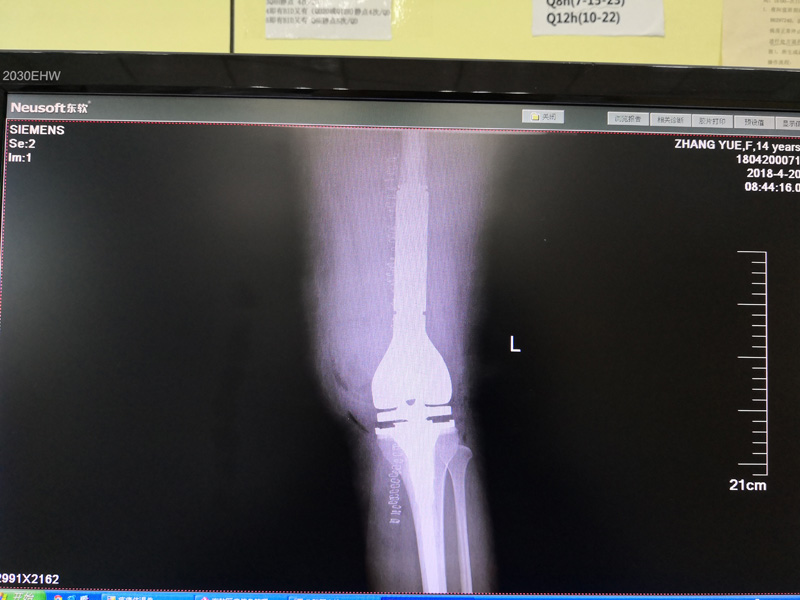

骨肉瘤手术手术后

患者张某,女,14岁,诊断为“左股骨远端骨肉瘤”,当地医院因为医疗技术和能力的限制,只能考虑截肢手术。患者家属通过平台推荐,指定到哈尔滨医科大学附属第二医院骨关节科找到陶树清主任就诊。经过严密、悉心的诊断,对小女孩还进行了“瘤段切除、肿瘤假体置换”手术,保留了小女孩肢体的健全,同时使她能够正常行走。

携生医疗骨肉瘤手术后X光片(侧位)

骨肉瘤手术后X光片(侧位)